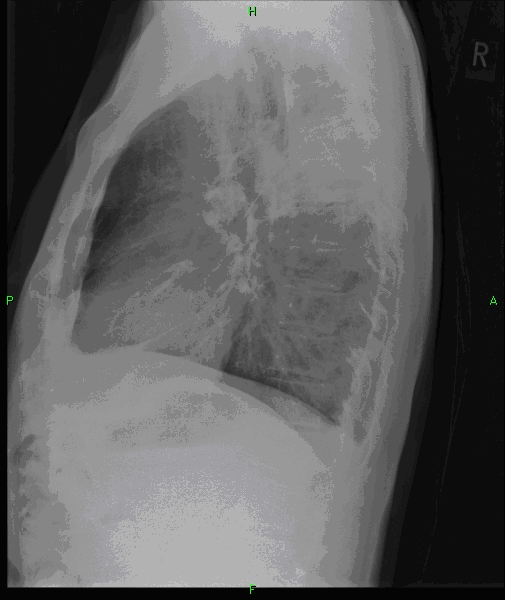

5a,b: Lung abscess. Chest radiograph, bidirectional (PA+lateral - right side near the film).

61 year old woman. Laparoscopic esophagus diverticulum resection 2 months ago. 7 cm air-fluid level with air space above: „basket sign” above the right diaphragm laterally measuring 2,5 cm in lateral diameter and 7 cm mediodorsally.